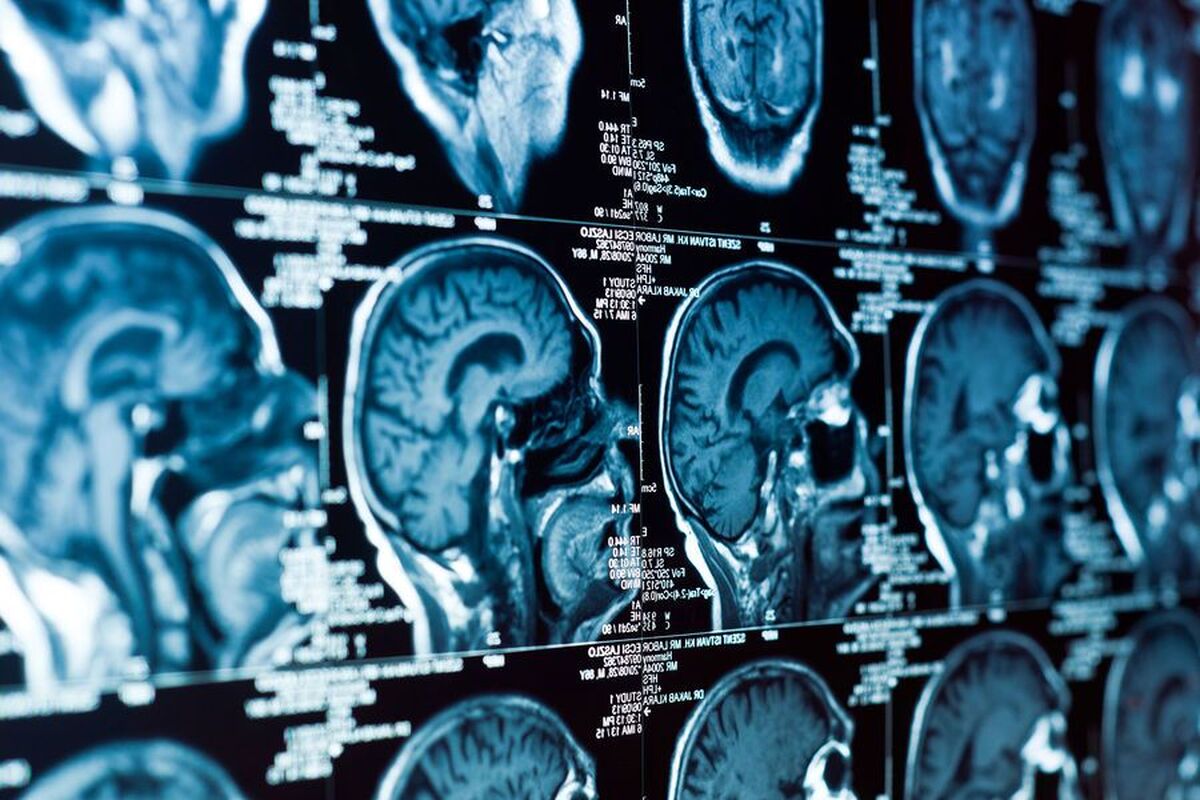

به گزارش مجله خبری نگار،در کودکان و نوجوانانی که مبتلا به اضطراب، افسردگی، ADHD و اختلالات رفتاری هستند، نواحی مغزی مسئول احساسات و پاسخ به تهدید کوچک می‌شوند. این نتیجه‌ای است که دانشمندان دانشگاه بث به آن رسیده‌اند. نتایج این مطالعه در مجله روانپزشکی زیستی (BioPsy) منتشر شده است.

دانشمندان داده‌های اسکن مغز نزدیک به ۹۰۰۰ کودک و نوجوان را تجزیه و تحلیل کردند. تقریباً نیمی از افراد مبتلا به یک اختلال روانی تشخیص داده شده بودند. هر چهار اختلال با تغییرات مشابهی همراه بودند: کاهش سطح در نواحی کلیدی درگیر در تنظیم احساسات و آگاهی از بدن. این نواحی شامل اینسولا، قشر انتورینال، شکنج گیجگاهی میانی و آمیگدال می‌شوند.